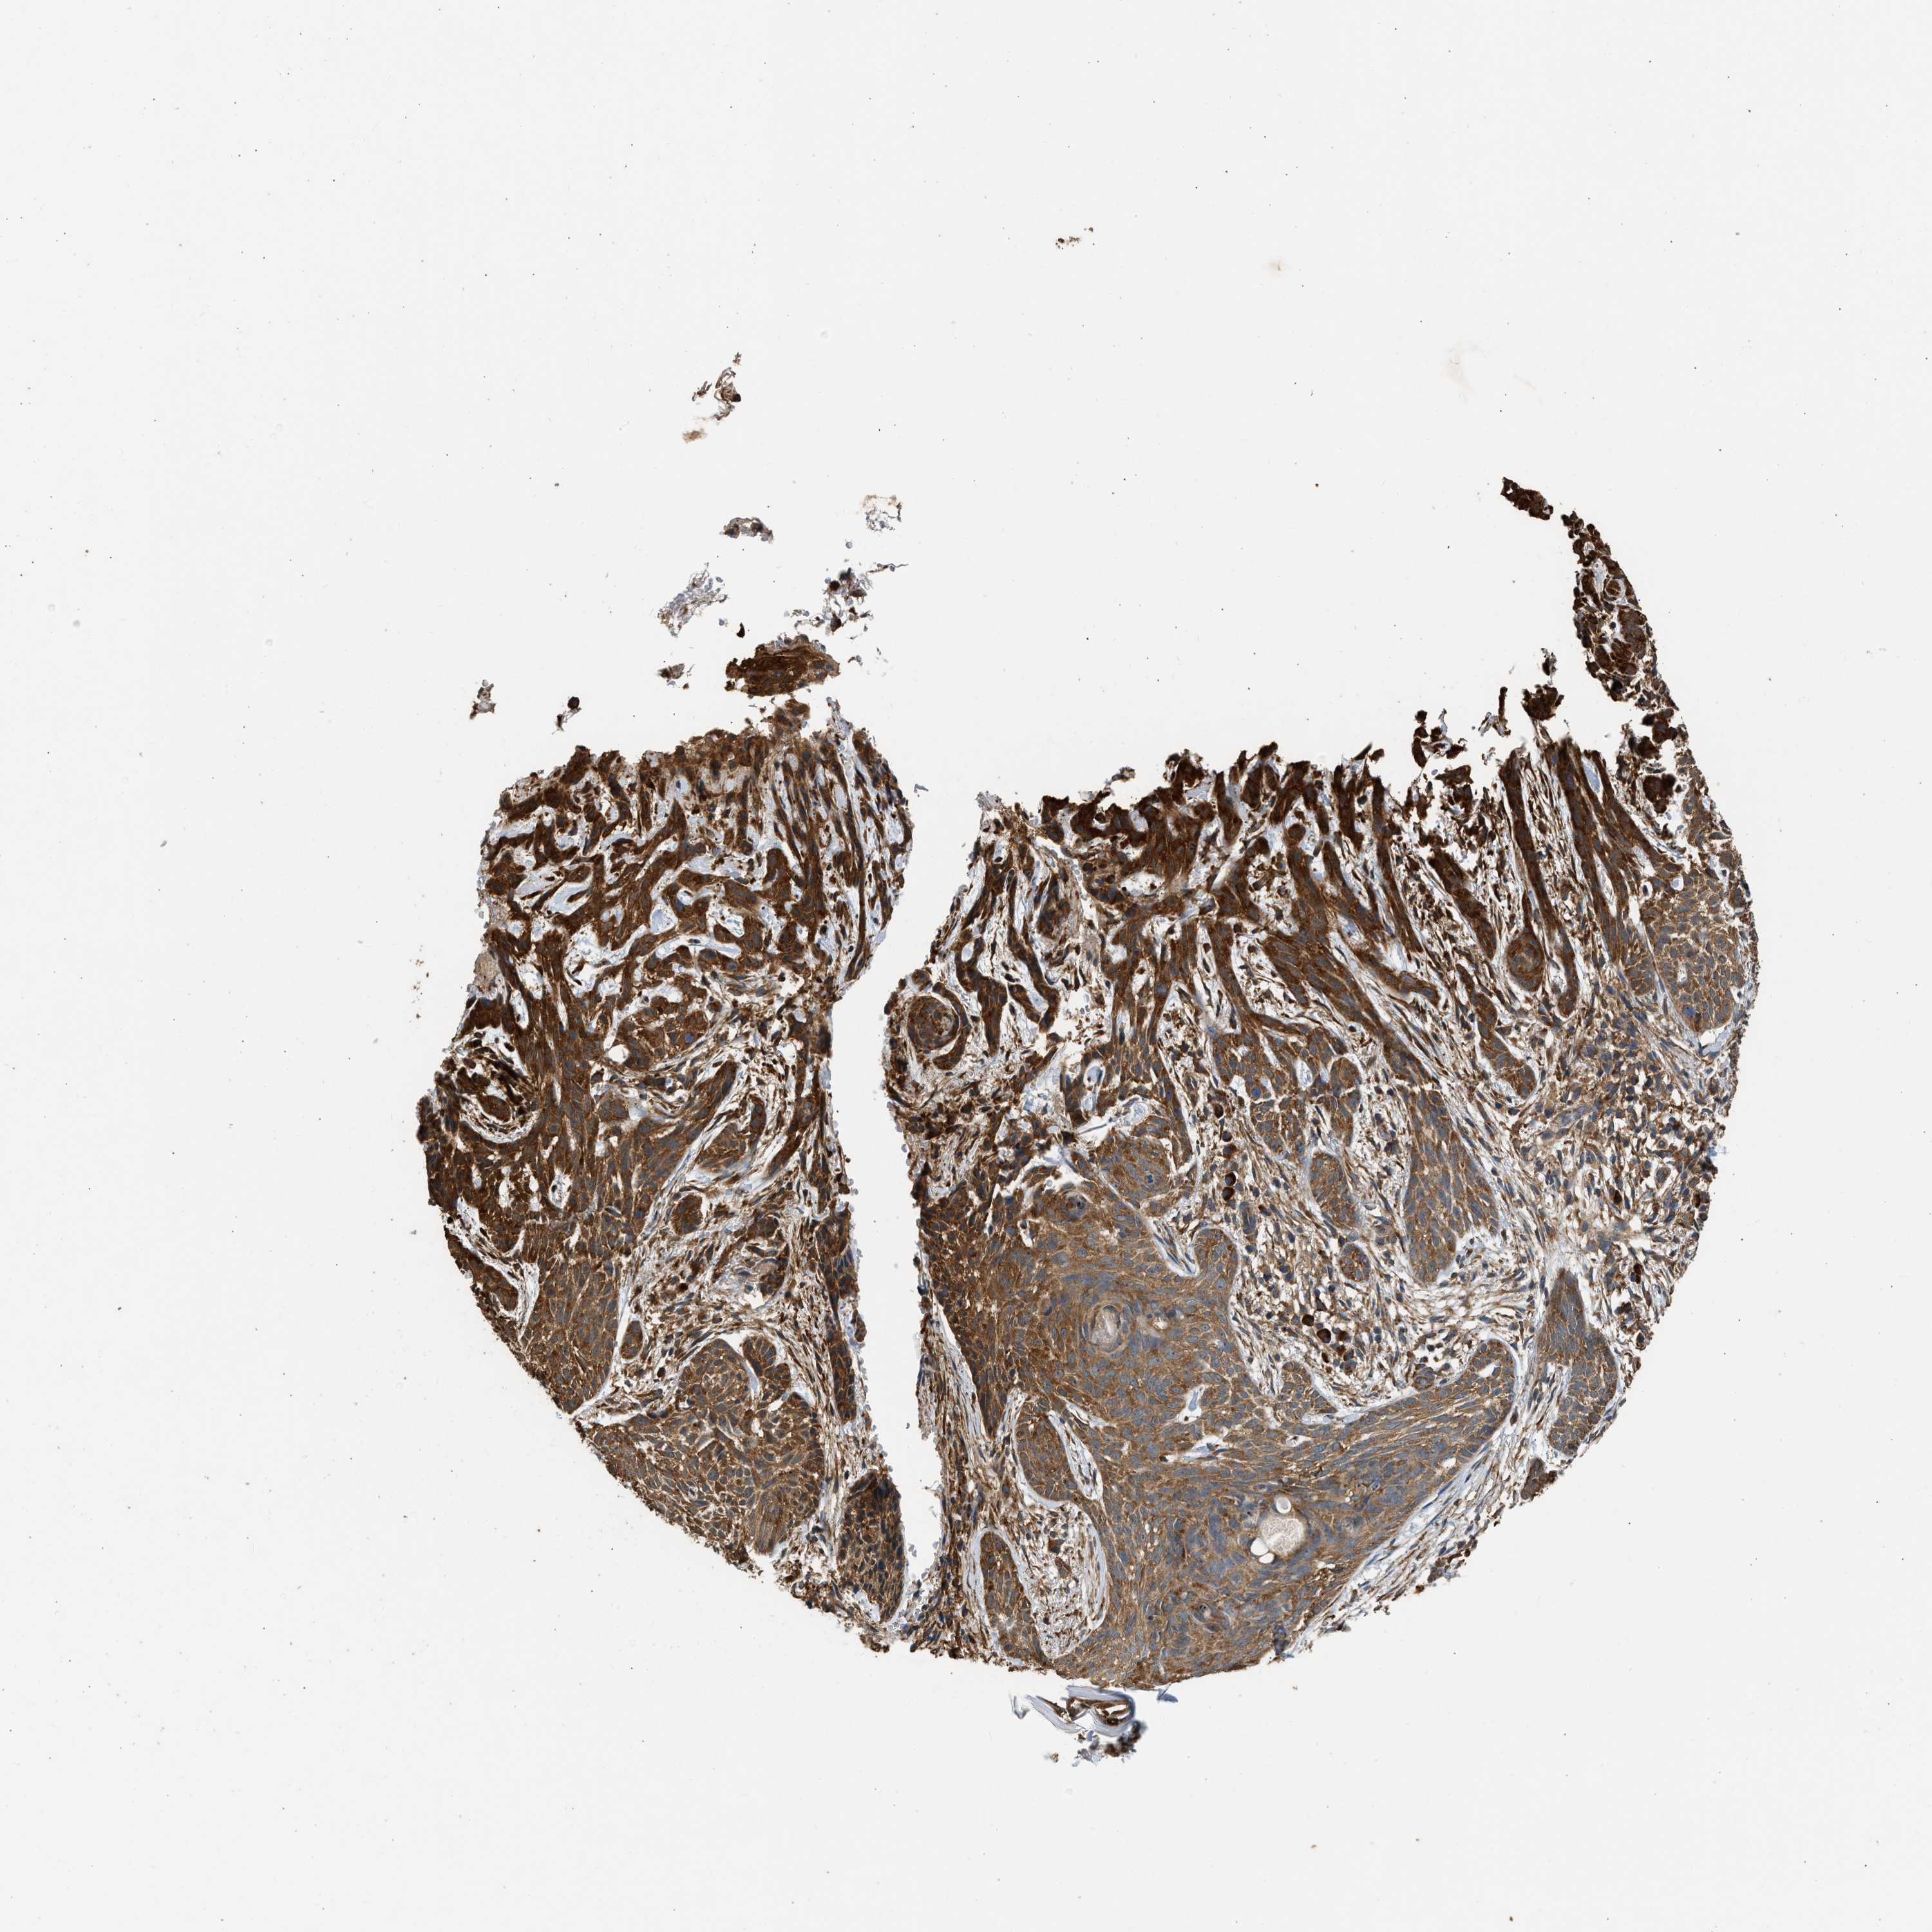

SKIN CANCER - Protein expressioni

A mouse-over function shows sample information and annotation data. Click on an image to view it in a full screen mode. Samples can be filtered based on level of antibody staining by selecting one or several of the following categories: high, medium, low and not detected. The assay and annotation is described here.

Antibody stainingi

Antibody staining in the annotated cell types in the current human tissue is reported as not detected, low, medium, or high, based on conventional immunohistochemistry profiling in selected tissues. This score is based on the combination of the staining intensity and fraction of stained cells.

Each image is clickable and will lead to virtual microscopy that enables deeper exploration of all samples and also displays staining intensity scores, fraction scores and subcellular localization as well as patient and tissue information for each sample.

Antibody HPA017887

Staining

High

Intensity

Strong

Quantity

>75%

Location

Cytoplasmic/membranous

Squamous cell carcinoma, NOS